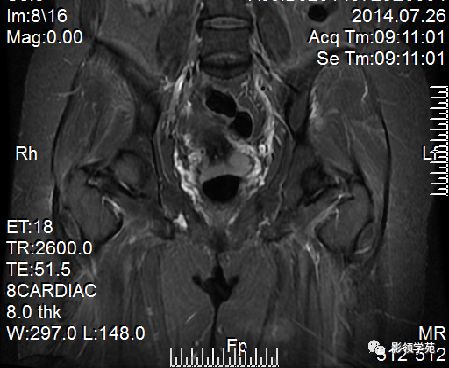

- Ⅱ期肿瘤:宫颈增大,宫旁肿块或宫旁脂肪组织内出现异常信号的粗线状影

- Ⅲ期肿瘤:侵犯至阴道下部,外延至盆壁,或出现肾积水。

DWI显示淋巴结肿大